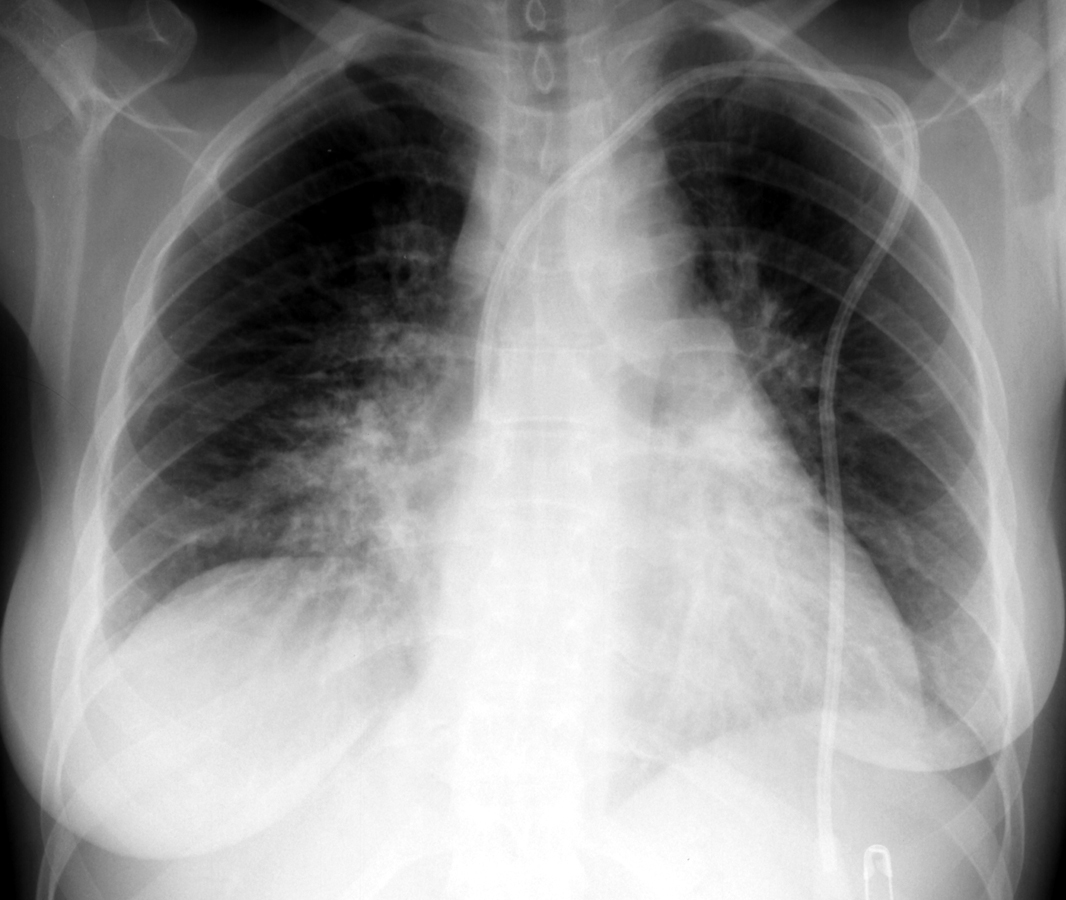

On CXR, a PTX appears as air without lung markings in the least dependant part of the chest. Generally, the air is found peripheral to the white line of the pleura. In an upright film this is most likely seen in the apices. A PTX is best demonstrated by an expiration film. It can be difficult to see when the patient is in a supine position. In this position, air rises to the medial aspect of the lung and may be seen as a lucency along the mediastinum. It may also collect in the inferior sulci causing a deep sulcus sign.

Apicolateral pneumothorax

Appears as a thin, white pleural line with no lung markings beyond. The presence of lung markings beyond this line, though, does not exclude pneumothorax. This is especially true in the patient with parenchymal disease which may alter the compliance of affected lobes, making their collapse more difficult to detect radiographically. Parenchymal disease may also make visualization of the pleural line more difficult or impossible.

Pneumothorax in the Supine Patient

In the supine patient, intrapleural air rises anteriorly and medially, often making the diagnosis of pneumothorax difficult. The anteromedial and subpulmonary locations are the initial areas of air collection in the supine patient. An apical pneumothorax in a supine patient is a sign that a large volume of air is present. Subpulmonic pneumothorax occurs when air accumulates between the base of the lung and the diaphragm. Anterolateral air may increase the radiolucency at the costophrenic sulcus. This is called the deep sulcus sign. Other signs of subpulmonic pneumothorax include a hyperlucent upper quadrant with visualization of the superior surface of the diaphragm and visualization of the inferior vena cava.